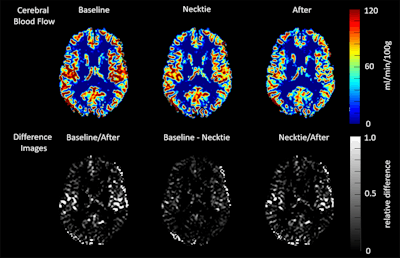

MR images show changes in cerebral blood flow in healthy volunteers before, during, and after wearing a necktie. Courtesy of Dr. Robin Lüddecke.Both groups received baseline MRI scans on a 3-tesla scanner (Achieva, Philips Healthcare). The control group received two more MRI scans, all without a necktie.

Each person in the experimental group underwent the baseline scan with an open collar and loosened necktie around his neck. The shirt collar was then closed and the necktie tightened for the second scan. Finally, for the third scan, the necktie was loosened and collar button opened.

The researchers used an arterial spin labeling (ASL) scanning protocol, with quantitative phase-contrast angiography performed over the jugular vein during a full RR cycle. Cerebral blood flow (CBF) was calculated and venous flow in the jugular vein was measured using software. CBF values were rendered as mL/min/100 g.

In the necktie group, cerebral blood flow dropped by 4.33 mL/min/100 g, or 7.5%, from the baseline scan to the second scan when the necktie was tightened. It was even lower at the third scan, 12.8% from baseline, after the necktie had been loosened. There were no statistically significant changes in CBF in the control group between the different scans.